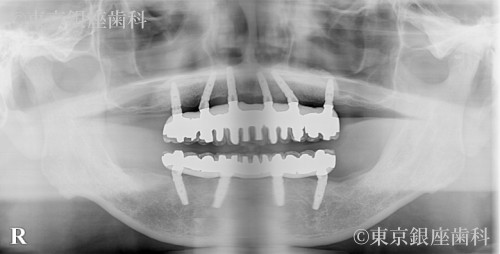

重度歯周病で骨が薄い状態から適切な固定を得て治療を進められた60歳代男性のインプラント症例

骨が薄く初期固定が困難と予測されたが、手術時に十分な固定が得られ入れ歯待機を回避。難症例ながら安定した治療結果に。

インプラント治療(骨吸収症例)